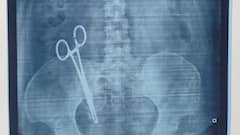

Lucknow Woman Discovers Surgical Scissors In Stomach 17 Years After C-Section